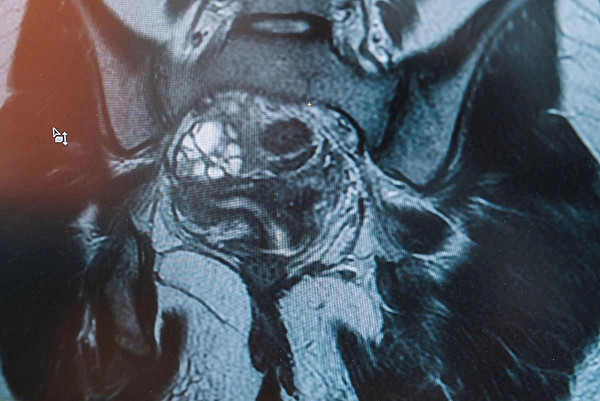

04.